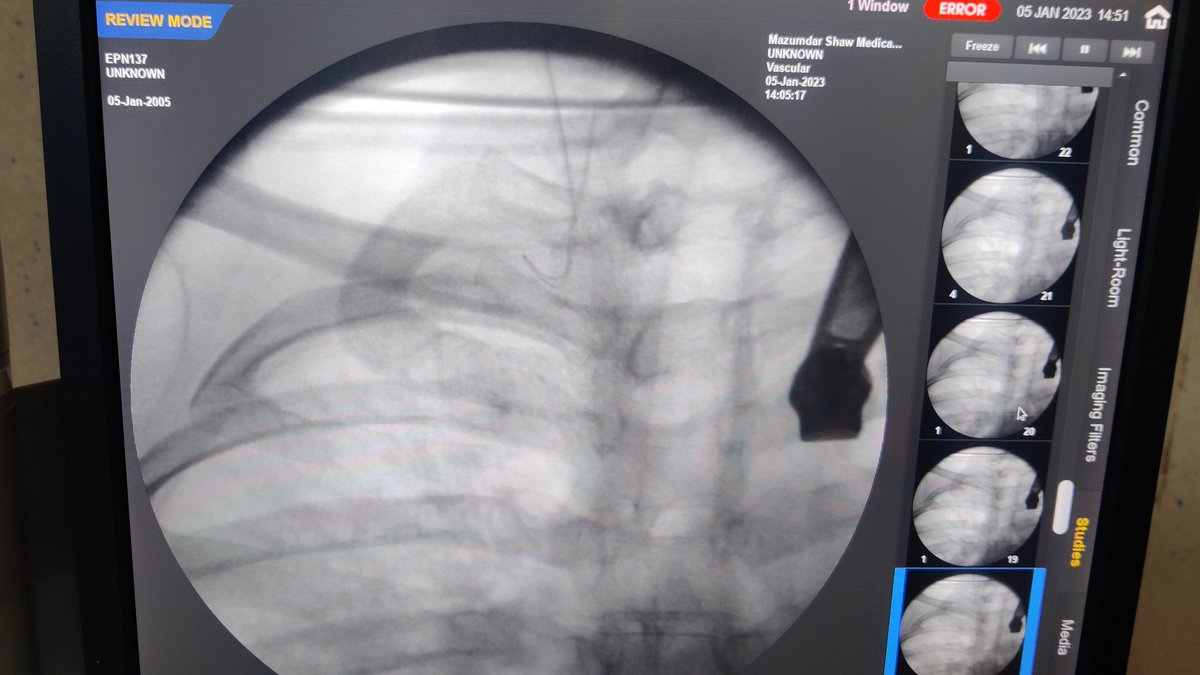

#micropuncture kit is such a boon for patients with thrombosed IJV Pic : 1 not able to pass the guidewire due to thrombus Pic 2: guidewire has gone after puncturing the thrombus with micropuncture guidewire Pic 3: final outcome @AVATAROrg @prashantnephro @fearingforties

Pic : 1 not able to pass the guidewire due to thrombus

Pic 2:  guidewire has gone after puncturing the thrombus with micropuncture guidewire

Pic 3: final outcome